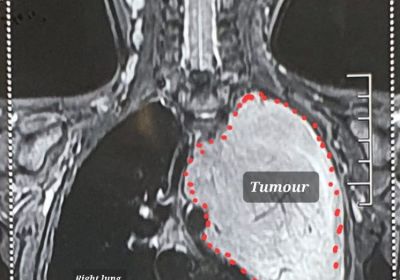

3 साल की मासूम 4 दिनों तक वेंटिलेटर सपोर्ट पर, फेफड़े से निकाला 1.5 किलोग्राम का ट्यूमर

26 Nov, 2023 09:11 AM IST | SAMWADINDIA.INरायपुर डॉ. भीमराव अम्बेडकर स्मृति चिकित्सालय रायपुर के हार्ट, चेस्ट और वैस्कुलर सर्जरी विभाग में 3...